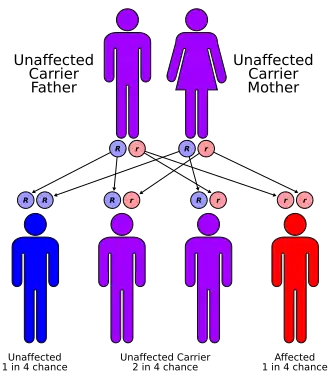

| ARPKD is inherited in an autosomal recessive pattern | |

Autosomal recessive polycystic kidney disease (ARPKD) is the recessive form of polycystic kidney disease. It is associated with a group of congenital fibrocystic syndromes.[5] Mutations in the PKHD1 (chromosomal locus 6p12.2) cause ARPKD.[6][7]

The cause of ARPKD is linked to mutations in the PKHD1 gene.[2] The PKHD1 gene encodes for the protein forfibrocystin, that is found in the epithelial cells of both the renal tubule and the bile ducts; deficiency leads to the characteristic polycystic dilation of both structures.[11]

ARPKD is a significant hereditary renal disease in that appears in childhood.[12] The prevalence is estimated to be of 1 in 20,000 live births,[12] with a reported carrier frequency of up to 1:70. PKHD1 is the only gene that is found to be responsible for the disease presentation of ARPKD.[12] PKHD1 is located on the human chromosome region 6p21.1–6p12.2.[12] It is also one of the largest genes in the genome as it occupies approximately 450 kb of DNA, and contains at least 86 exons.[12]

It is known that FPC interacts with ADPKD protein PC2 and may also participate in this regulation pathway of the mechanosensory function of the primary cilia, calcium signaling, and PCP.[12] This is suggesting a common mechanism underlying cystogenesis between ADPKD and ARPKD.[12] The FPC protein is also found on the centrosomes and mitotic spindle and may regulate centrosome duplication and mitotic spindle assembly during cell division.[12] There have been a large number of various single-gene mutations found throughout PKHD1 and are unique to individual families. Most of the patients are compound heterozygotes for PKHD1 mutations.[12] Patients with two nonsense mutations appear to have an earlier onset of the disease.[12]